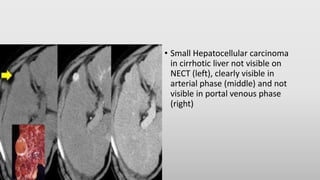

• Small Hepatocellular carcinoma

in cirrhotic liver not visible on

NECT (left), clearly visible in

arterial phase (middle) and not

visible in portal venous phase

(right)

• Small Hepatocellularcarcinoma in cirrhotic liver not visible on NECT (left), clearly visible in arterial phase (middle) and not visible in portal venous phase (right)